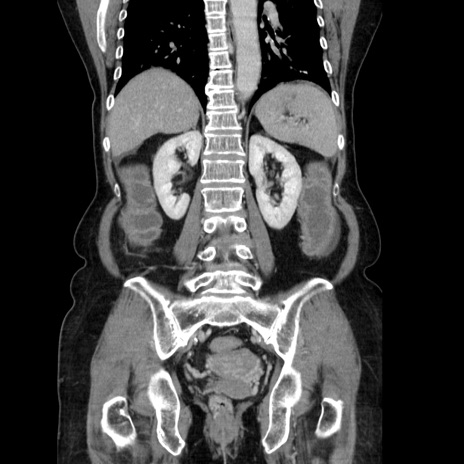

症例5(冠状断像)

【症例】70歳代女性

【主訴】お腹が張る

【現病歴】1週間くらい前から腹部膨満の自覚あり。昨日夜から増悪したため、本日救急外来受診。

【身体所見】意識清明、BT 36.5℃、BP 165/106mmHg、HR 80bpm、SpO2 98%、腹部:膨満、軟、自発痛・圧痛なし、触診にて不快感あり、腸蠕動音:減弱

【データ】WBC 12600、CRP 1.04